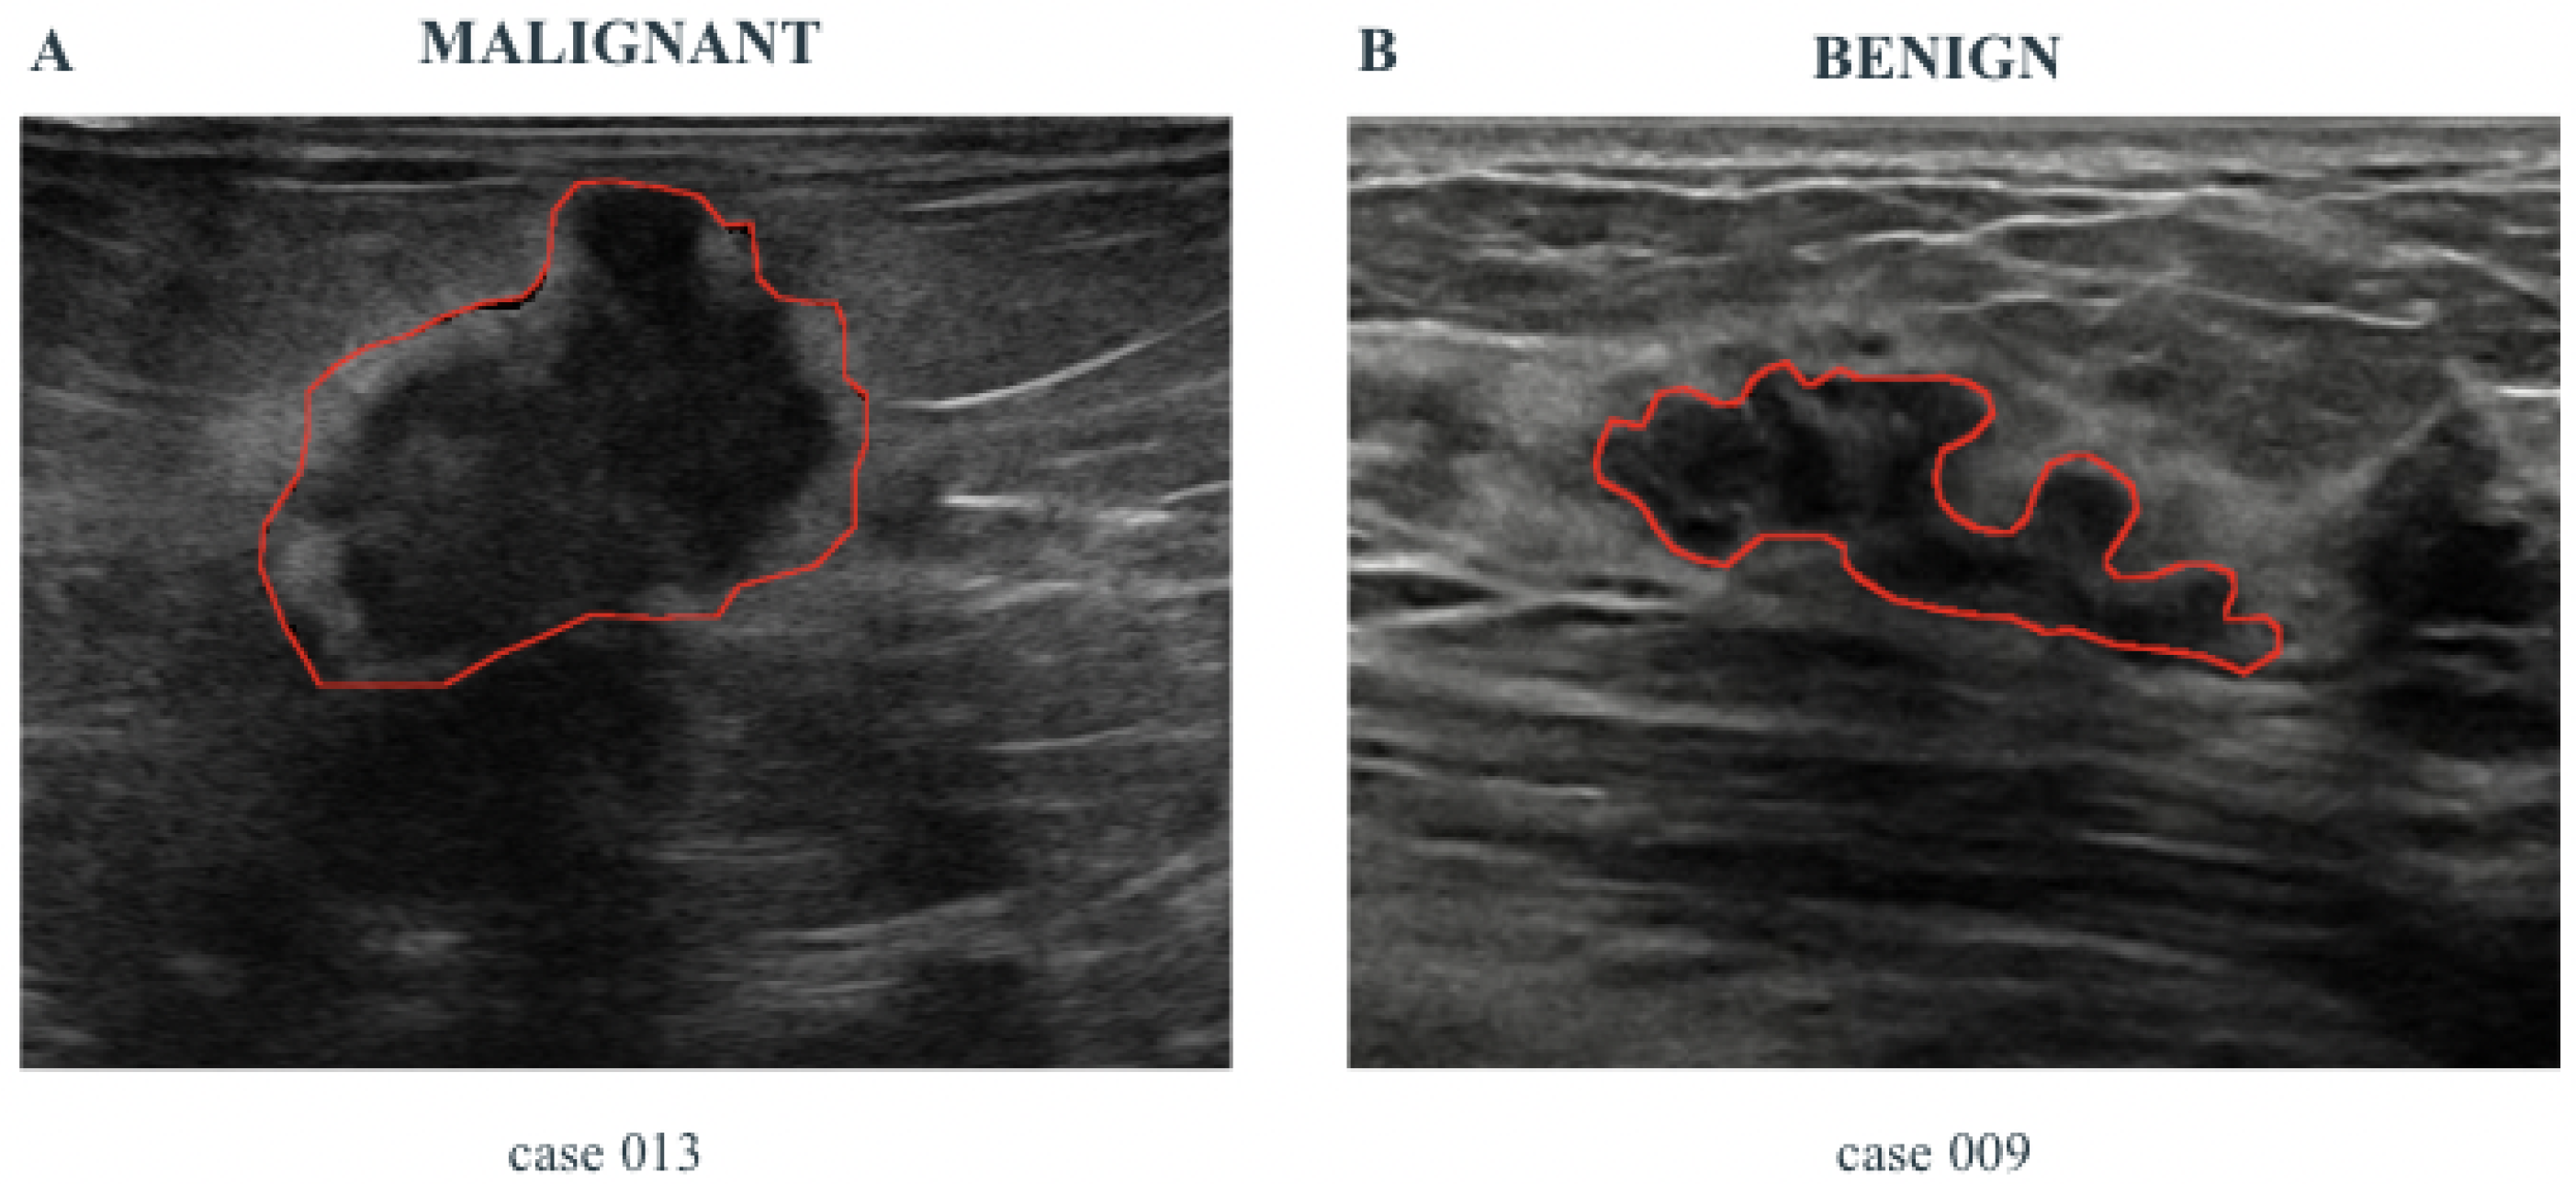

4.1. Implementation of DIAM in the Breast Cancer Case

- Some specific features related to the pathology, namely Pathological Features (PFs), are automatically extracted from the images by using properly designed Computer Vision algorithms. These features are shown to the healthcare professionals and are useful to support the diagnosis.

- A risk assessment, computed by using suitably designed ML algorithms. For the computation of AI-based risk assessment, the ML methods use a set of features automatically extracted from US images, larger than PF, and called Hand-crafted Features (HFs).